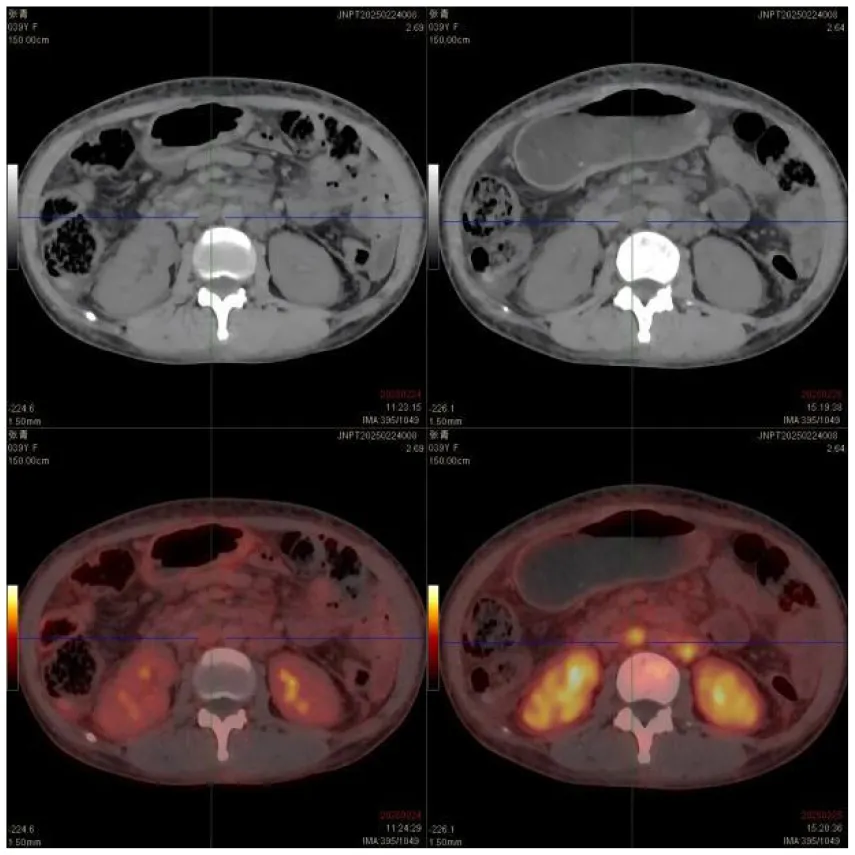

(II) PET/CT: ① Multiple enlarged lymph nodes (bilateral neck I–V, axillae, hila, mediastinum, abdomen, retroperitoneum, and iliac vessels) with mildly increased fluorodeoxyglucose (FDG) uptake and variable C-X-C chemokine receptor type 4 (CXCR4) expression; ② Splenomegaly with diffuse CXCR4 expression, normal FDG uptake; ③ Diffusely increased FDG uptake and CXCR4 expression in bones, suggesting hypercellular marrow; ④ Peritonitis, scattered ascites; ⑤ Subcutaneous edema in neck/chest/abdomen/pelvis/bilateral thighs/buttocks.

| PET/CT: | ① Multiple enlarged lymph nodes in bilateral neck I–V area, bilateral axilla, bilateral hilar region, mediastinum, abdominal cavity, retroperitoneum, and bilateral iliac vascular pathway area, mild increase in FDG metabolism, increased expression of CXCR4 to varying degrees; multiple enlarged lymph nodes ② Enlarged spleen, CXCR4 expression increased diffusely | |

| Thorax CT | Multiple enlarged lymph nodes were found in the right heart diaphragmatic angle, intra-abdomen, and retroperitoneum, which were larger than the anterior part; bone density was increased in the sternum, some vertebrae and pelvis, and bilateral femur; a small amount of fluid was found in both pleural cavities, and scattered inflammation was detected in both lungs | |

| Abdomen CT | Multiple enlarged lymph nodes were found in the right heart diaphragmatic angle, intra-abdomen, and retroperitoneum, which were larger than the anterior part; bone density was increased in the sternum, some vertebrae and pelvis, and bilateral femur; a small amount of fluid was found in both pleural cavities, and scattered inflammation was detected in both lungs. Multiple enlarged lymph nodes were found in the right heart diaphragmatic angle, intra-abdomen, and retroperitoneum, which were larger than the anterior part; bone density was increased in the sternum, some vertebrae and pelvis, and bilateral femur; a small amount of fluid was found in both pleural cavities, and scattered inflammation was detected in both lungs | |

CT images of the patient's abdomen.

A and B are abdominal CT scan images before and after autologous stem cell transplantation. A shows a significant amount of ascites, while B indicates a marked reduction in ascites. C, D, and E are PET/CT images before autologous stem cell transplantation, which show increased bone density in multiple areas, elevated FDG metabolism, no abnormal increase in CXCR4 expression; splenomegaly with diffusely increased CXCR4 expression and no abnormal FDG metabolism; and inflammatory changes in the peritoneum with scattered effusions in the abdomen and pelvis. F shows improvement after treatment.